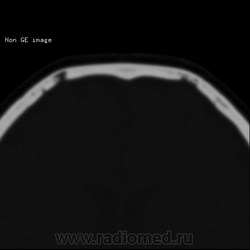

Изменение костей черепа, КТ.

Нейрохирург принес на консультацию снимки. Пациенту был выставлен диагноз в частном диагностическом центре эозинофильная(-ные) гранулёмы лобных костей. Как вам?

А, не совпадают ли эти "гранулёмы" топографически с венозными выпускниками?

Пахионовы ямки. Валентин Львович, Вы первый.

Согласна, конечно пахионовые грануляции.

Конечно же это не эозинофильные гранулёмы, пациента прислали к нейрохирургу, предварительно расстроив.

Вижу эти образования как ямочки грануляций, сообщающиеся с диплоетическими венами

Пахионовы грануляции, конечно! Еще они иногда вдаются в просвет венозных синусов, и тогда рентгенологи пишут "тромбоз")